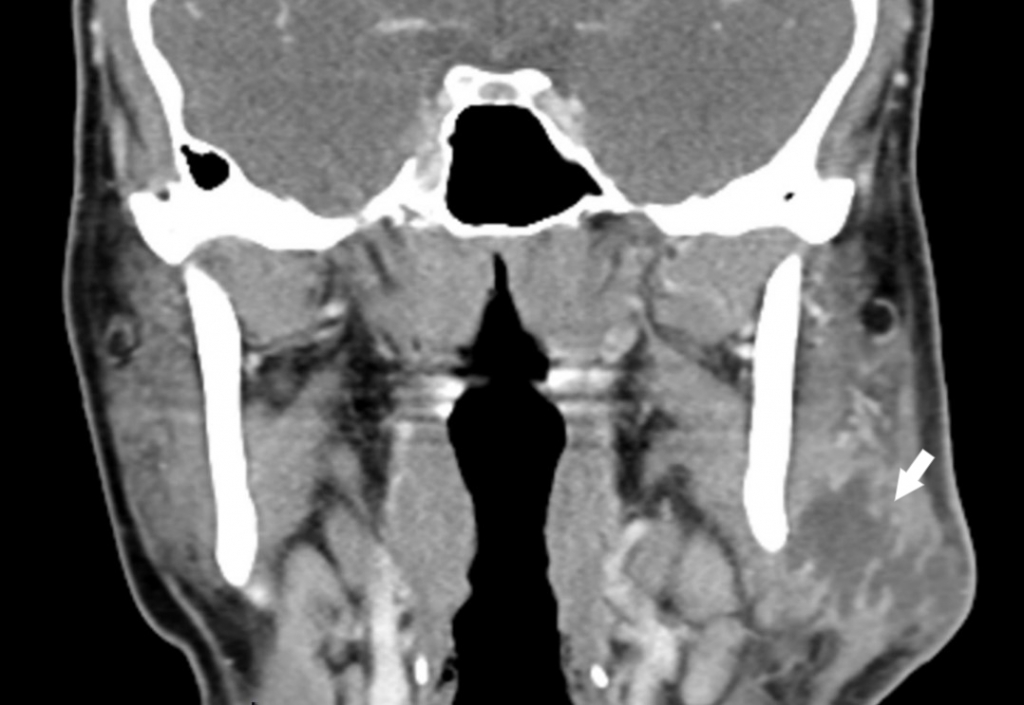

Trismus was present, with restricted and painful mouth opening of approximately 2 cm. Serous saliva of normal consistency was observed flowing from the Stensen’s duct orifice. No additional significant findings were noted on physical examination. Neck ultrasonography revealed a dense fluid collection of approximately 3×2 cm within the left parotid gland, suggestive of an abscess. To further evaluate potential post-traumatic fractures, the extent of abscess spread, its origin, and involvement of cervical spaces, contrast-enhanced neck computed tomography (CT) was performed. A well-defined collection measuring approximately 3 cm in diameter, consistent with an isolated abscess within the left parotid gland, was observed (Figure 2).